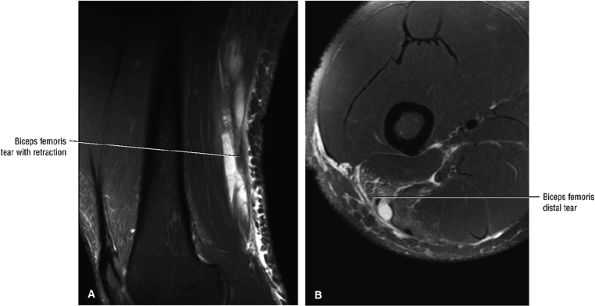

Grade 3: Complete rupture of the MTU (Fig. 3.108)

Grade 2: Hyperintense hemorrhage with tearing and disruption of up to 50% of the muscle fibers. Interstitial hyperintensity with focal hyperintensity represents hemorrhage in the muscle belly with or without intramuscular fluid (Figs. 3.111 and 3.112). A hyperintense focal defect and partial retraction of muscle fibers may also be visualized. Associated myotendinous and tendinous injuries as well as hyperintensity and interruption and widening of the MTU are also found.

Grade 3: Complete tearing with or without muscle retraction (Fig. 3.113). A fluid-filled gap can be seen, which is hyperintense on FS PD FSE and STIR images. Associated adjacent hyperintense interstitial muscle changes may also be depicted.